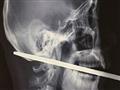

نشرت صحيفة "ديلي ميل" البريطانية، صورة عامل بناء نجا من الموت بأعجوبة بعد سقوطه علي سيخ معدني اخترق رأسه عرضياً.

كان عامل البناء الصيني ىالبالغ من العمر 25 عاماً يسير علي منصة بناء ارتفاعها مرتين تقريباً خلال عمله حينما سقط علي السيخ المعدني، فاخترق السيخ رأسه من وجنته وخرج من الجزء الخلفي من الجمجمة.

ونجح الأطباء بعد جراحة شاقة في انقاذ حياته، وعبر أحد الأطباء عن اندهاشه بنجاة المريض دون أن يصيب السيخ الشرايين الحيوية مما كان سيؤدي إلي مقتله أو عماه علي الأقل.

واستأصل الأطباء أثناء الجراحة جزء من الجمجمة لازالة السيخ الذي بلغ طوله 30 سم.